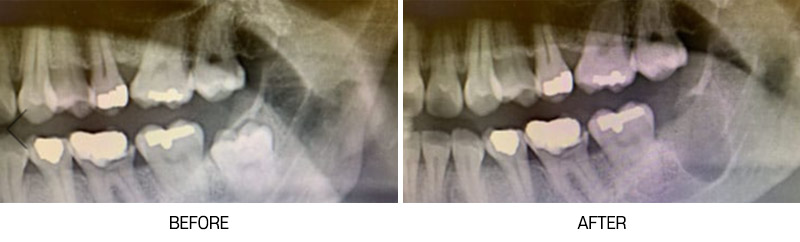

전후사진

• [사랑니] 매복발치

사랑니/매복발치